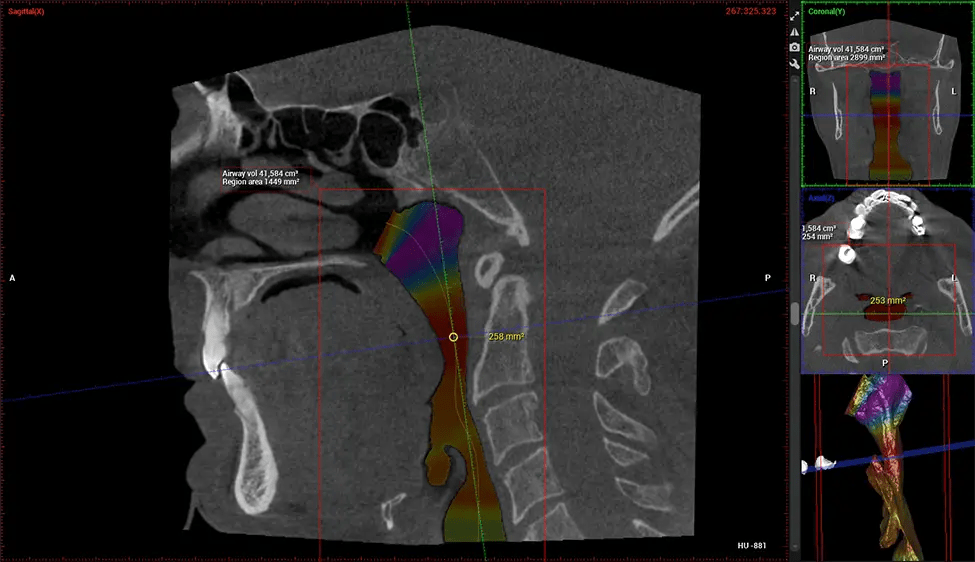

There are many benefits to using CBCT technology, especially compared to the traditional 2D X-ray format. One of the most significant advantages of CBCT scans is that they provide much more information than traditional X-rays. A scan lets your dentist see images from all angles of your jaw and mouth, including your sinuses, nasal cavity, cheekbones, and other surrounding areas. This added information helps your dentist craft a comprehensive treatment plan that addresses all aspects of your oral health.

Planmeca Viso G7 CBCT ( Cone Beam CT Scan ) is designed to surpass the demands of industry leaders, specialists, and large institutions. It’s has a large ø25×30 cm sensor with four built-in cameras. It can capture unlimited volume sizes from a ø3×3 cm to a ø30x30cm volume capturing the skullcap through C7 on the cervical spine. The Planmeca Viso G7 offers the industry’s largest single volume scan of ø30×19 cm. It’s poised to handle advanced imaging modalities such as Planmeca ProFace® and Planmeca 4D™ Jaw Motion technology. The occipital head support allows an unimpeded view of facial tissue.

Planmeca is the only manufacturer clinically proven to dramatically reduce patient radiation without sacrificing image quality. Planmeca Ultra Low Dose™ achieves an average reduction in dose of 77% without a statistical reduction in image quality allowing doctors to incorporate 3D imaging into routine protocols with effective patient radiation often lower than 2D intraoral imaging. This increases patient care, allows doctors to diagnose more dentistry, and often earlier in disease progression, than with 2D imaging alone.